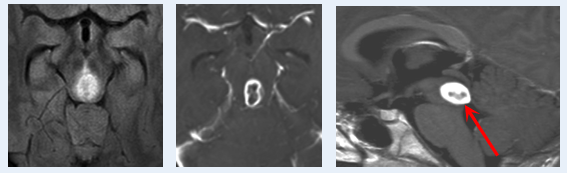

术前MRI

这种肿瘤通常边界不明,而成功切除肿瘤的前提恰好是精准找到边界。切多了,人就毁了,而切少了,就易复发。

“我们可以从肿瘤的质地而不是其他特征看出肿瘤的边界。”

在手术室里,巴教授的手指精准感知着肿瘤的质地变化——“这里!边界就在这里!”没有依赖5-ALA荧光染色,因为在脑干胶质瘤中很难用。巴教授凭千台手术锤炼出的“手感”,他像拆除脑中的炸弹般,精确剥离肿瘤。这种分辨出肿瘤与神经的微妙界限的能力,也是一种超绝感知力。

术后MRI

成功手术,当时术后病理为间变性星形细胞瘤。那个连路都走不稳的少年,活过了15年!